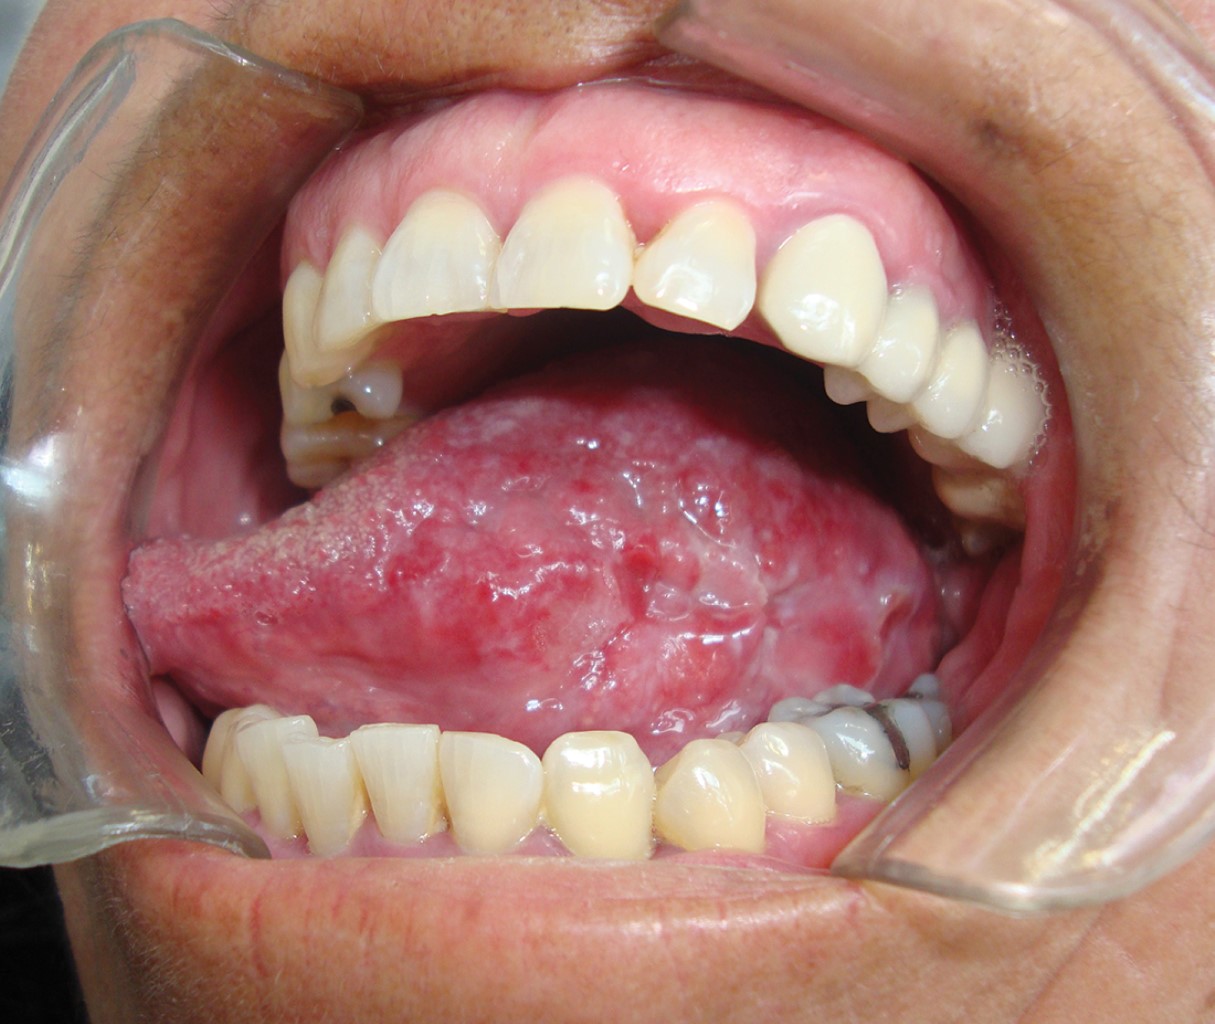

Según Scully, los carcinógenos como las nitrosaminas específicas del tabaco, los hidrocarburos, algunos metales y radicales libres, bloquean a las enzimas antioxidantes glutatión-S-transferasa, el glutatión reductasa, el superóxido dismutasa y la glutatión peroxidasa.13 El tabaco y el consumo de alcohol se han implicado en el desarrollo de carcinomas bucales de células escamosas, siendo más frecuente en el borde lateral de la lengua (Figura 2).15

El cáncer de la cavidad oral comprende los labios, la mucosa vestibular y las glándulas salivares.8 El COCE afecta la mucosa bucal, encía, paladar duro y blando, lengua y piso de la boca.10 El carcinoma bucal de células escamosas representa 2% de todos los tipos de cáncer, casi 30% de los tumores malignos; el COCE representa alrededor de 90% de cáncer de la cavidad oral. La localización más común es en el borde lateral de la lengua.8 La enfermedad afecta en mayor parte a personas mayores, en su gran mayoría del sexo masculino, a partir de los 40 años con un pico máximo a la edad de 60 años al momento de diagnosticar (Figura 1).12